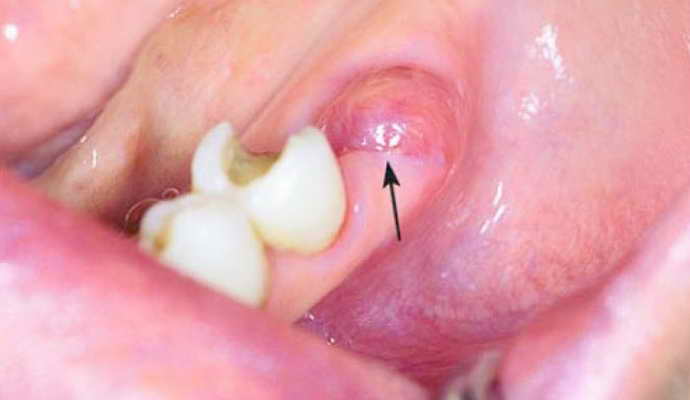

«Сухая лунка» после удаления зуба

- сформировалось явление, получившее название «сухая лунка». Происходит нарушение целостности защитного сгустка или его полная потеря из-за несоблюдения предписаний врача, чрезмерно интенсивного полоскания полости рта, повреждения лунки щеткой или твердой едой,